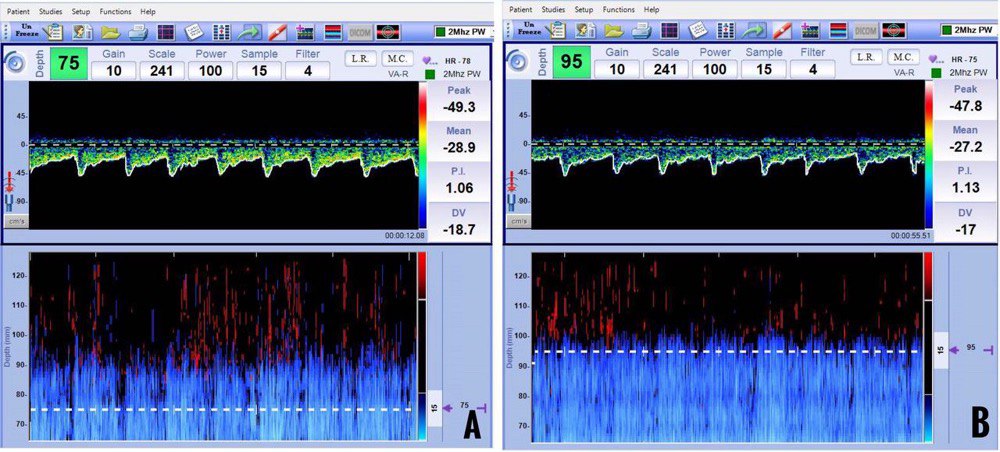

Velocity criteria for vasospasm in MCA have been well established. An MFV of more than 120 cm/sec suggests vasospasm in the clinical context of aneurysmal SAH. Severe vasospasm is suspected when MFV is more than 200 cm/sec. Sometimes, only a gradual increase in flow velocities per day (more than 50 cm/sec) is observed in the first few days after aneurysmal rupture. One important differential diagnosis for increased velocities is hyperemia. It is important to look at velocities in extracranial circulation to differentiate vasospasm and hyperemia reliably. The LR has been developed specifically for this purpose. A MFV of more than 120 cm/sec and a LR of more than 3 indicate vasospasm (Figure 13).

Figure 13: Elevated mean flow velocities in the middle cerebral artery (A) and normal mean flow velocities in the extracranial internal carotid artery (B). The calculated Lindegaard Ratio is 4.6 and suggestive of mild-moderate vasospasm.

A MFV of more than 80 cm/sec and 95 cm/sec suggest vasospasm in vertebral and basilar arteries, respectively. A modified LR of more than two differentiates hyperemia and vasospasm in the basilar artery. The velocities of ACA and PCA have not been standardized because of collateral flows through ACOM and PCOM, respectively.